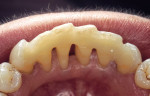

In vitro studies have demonstrated that the use of unidirectional glass-fiber reinforcement in the connector areas of FPDs contributes to significant composite reinforcement.29,36-38,66-68 Similar findings have been reported with a leno-weave UHMWPE and triaxial weave UHMWPE fiber.20,33,36 Fiber-reinforcing materials used by a dental laboratory are either resin pre-impregnated glass fibers, pre-polymerized composite resin surrounding glass fibers, biaxial braid UHMWPE, leno-weave UHMWPE, or a triaxial weave UHMWPE (Table 3). Typically, the preparation designs for the abutment teeth are inlay or onlay preparations (Figure 6A, Figure 6B, Figure 6C, Figure 6D). They are highly successful and can provide the patient with clinical service for more than 5 to 10 years.69 These restorations must be cemented using an adhesive resin technique with resin cements. Both etch-and-rinse adhesives with a self-cure or dual-cure composite resin cement or with a self-adhesive resin cement are indicated for cementing these restorations (Figure 7).36-38,70 Also, fiber-reinforcing materials are being used by dental laboratories in the fabrication of provisional restorations to reinforce and strengthen acrylic and composite-resin provisional materials.15,40,71